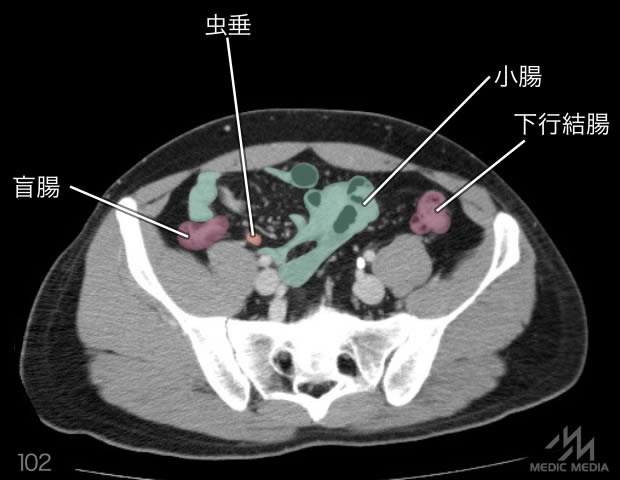

造影CT

スライド(画像下)を動かしながら,CTで臓器の位置を確認してみましょう.

消化器

肝区域